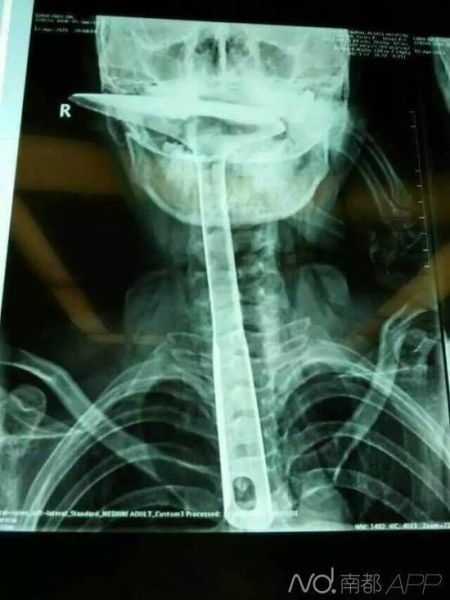

陳女士被緊急送到東莞第五人民醫(yī)院,醫(yī)生拍片顯示,整個(gè)鐵鍋鏟把手已經(jīng)在胸里了,病情嚴(yán)重。當(dāng)晚,陳女士就被轉(zhuǎn)到了康華醫(yī)院。

“患者來(lái)院時(shí),嘴巴里只剩一個(gè)鍋鏟鏟勺露在外面,整個(gè)鍋鏟手柄已經(jīng)被插入到食道里了。”康華醫(yī)院胸外科接診醫(yī)生陳羽彪說(shuō),檢查發(fā)現(xiàn),鍋鏟總長(zhǎng)大概30公分長(zhǎng),手柄直徑約2.5公分,整個(gè)已經(jīng)插入食道,食道表皮粘膜損傷嚴(yán)重,且被捅破了一個(gè)洞,“而且,手柄已嚴(yán)重?cái)D壓到了肺部,導(dǎo)致右肺部已無(wú)法正常擴(kuò)張”。

“這樣的病例,不說(shuō)100年難遇,也是50年難遇了。”康華醫(yī)院胸外科主任肖樸說(shuō),患者情況嚴(yán)重,醫(yī)院立即組織專家會(huì)診。“胸腔全是大血管,一旦拔出就有可能大出血,危及性命。”